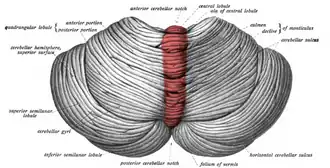

Upper surface of cerebellum. The vermis is highlighted in red. | |

The cerebellar vermis (from Latin vermis, "worm") is located in the medial, cortico-nuclear zone of the cerebellum, which is in the posterior fossa of the cranium. The primary fissure in the vermis curves ventrolaterally to the superior surface of the cerebellum, dividing it into anterior and posterior lobes. Functionally, the vermis is associated with bodily posture and locomotion. The vermis is included within the spinocerebellum and receives somatic sensory input from the head and proximal body parts via ascending spinal pathways.[1]

Structure

The vermis is the unpaired, median portion of the cerebellum that connects the two hemispheres.[9] Both the vermis and the hemispheres are composed of lobules formed by groups of folia. There are nine lobules of the vermis: lingula, central lobule, culmen, clivus, folium of the vermis, tuber, pyramid, uvula and nodule.[9] These lobules are often difficult to observe during human anatomy classes and may vary in size, shape and number of folia. It has been shown that folia of the cerebellum exhibit frequent variations in form, number and arrangement between individuals.[9]

Lobe anatomy

The lingula is the first lobule of the upper portion of the vermis on the superoinferior axis and pertains to the paleocerebellum together with the central lobule, culmen, pyramid and uvula. It is separated from the central lobule by the pre-central fissure. The central lobule is the second lobule of the upper portion of the vermis on the superoinferior axis. The culmen is the third and largest lobule of the upper portion of the vermis on the superoinferior axis. It is separated from the declive by the primary fissure and is related with the anterior quadrangular lobule of the hemisphere. The pyramid is the seventh lobule of the vermis on the superoinferior axis. It is separated from the tuber and uvula by the pre-pyramidal and secondary fissures, respectively.[9] This lobule is related with the biventral lobule of the hemisphere. The uvula is the second largest lobule, following the culmen. It pertains to the paleocerebellum and is separated from the nodule by the posterolateral fissure.[9]